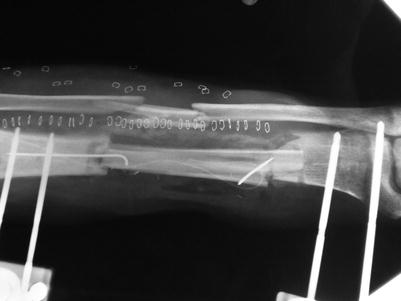

Fig. 23.12

Procedure 12: The tip of the bone is shaved, inserted into the marrow at both ends and fixed in place with a steel wire. Side-to-end anastomosis is conducted of the vascular pedicle to the posterior tibial blood vessels